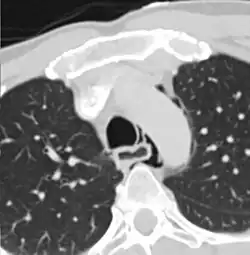

Axial CT image through the upper chest showing extraluminal air (Pneumomediastinum) surrounding the trachea and esophagus | |

The diagnosis of Boerhaave syndrome is suggested on the plain chest radiography and confirmed by chest CT scan. The initial plain chest radiograph is almost always abnormal in patients with Boerhaave syndrome and usually reveals mediastinal or free peritoneal air as the initial radiologic manifestation. With cervical esophageal perforations, plain films of the neck show air in the soft tissues of the prevertebral space.

Hours to days later, pleural effusion(s) with or without pneumothorax, widened mediastinum, and subcutaneous emphysema is typically seen. CT scan may show esophageal wall edema and thickening, extraesophageal air, periesophageal fluid with or without gas bubbles, mediastinal widening, and air and fluid in the pleural spaces, retroperitoneum or lesser sac.